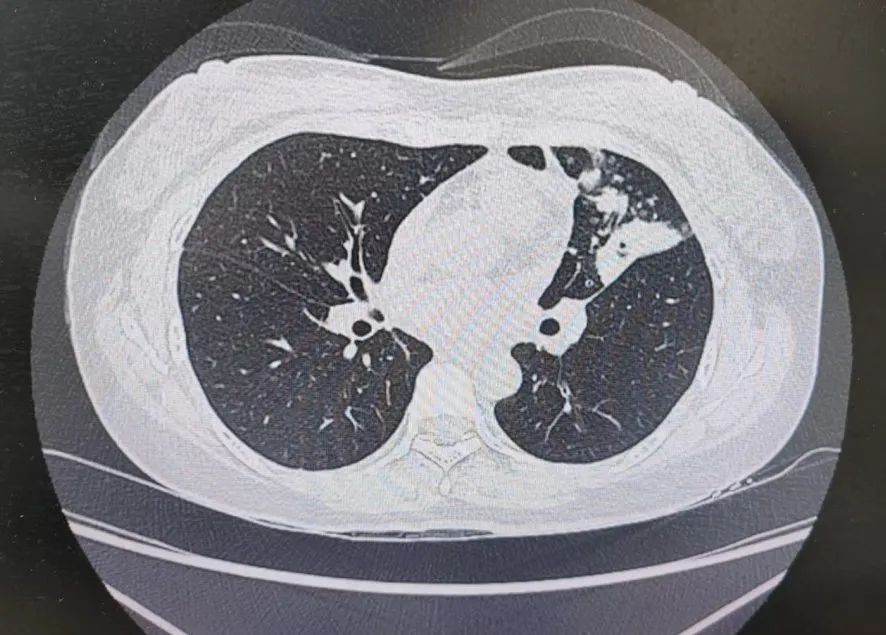

患者肺部CT影像

“一般来说,肺炎经过一周的抗感染治疗,病灶会有所吸收。但陈女士的肺部阴影纹丝不动,这种情况必须提高警惕。”宋刚主任团队立即启动了更深入的“三部精准诊断”程序:

3、CT引导下穿刺活检:病理诊断为左肺上叶腺癌。

肺炎型肺癌,因其影像学表现与普通肺炎极为相似,临床上误诊率极高。然而确诊仅是第一步。宋刚主任当天即召集肿瘤科、病理科、影像科等多学科专家会诊,为陈女士制定个体化治疗方案。